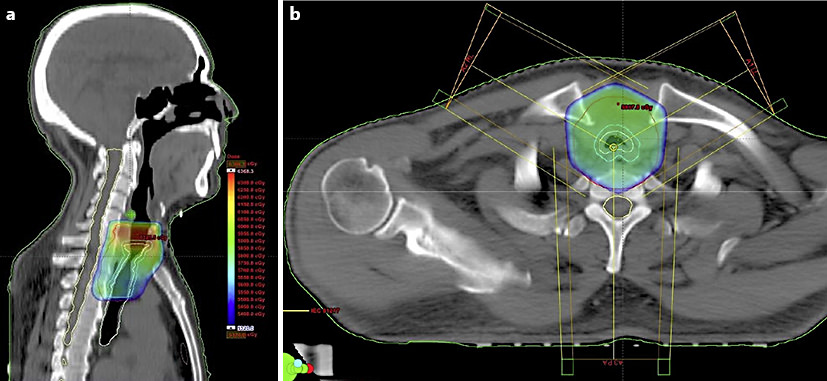

Tracheal SCC Survivor